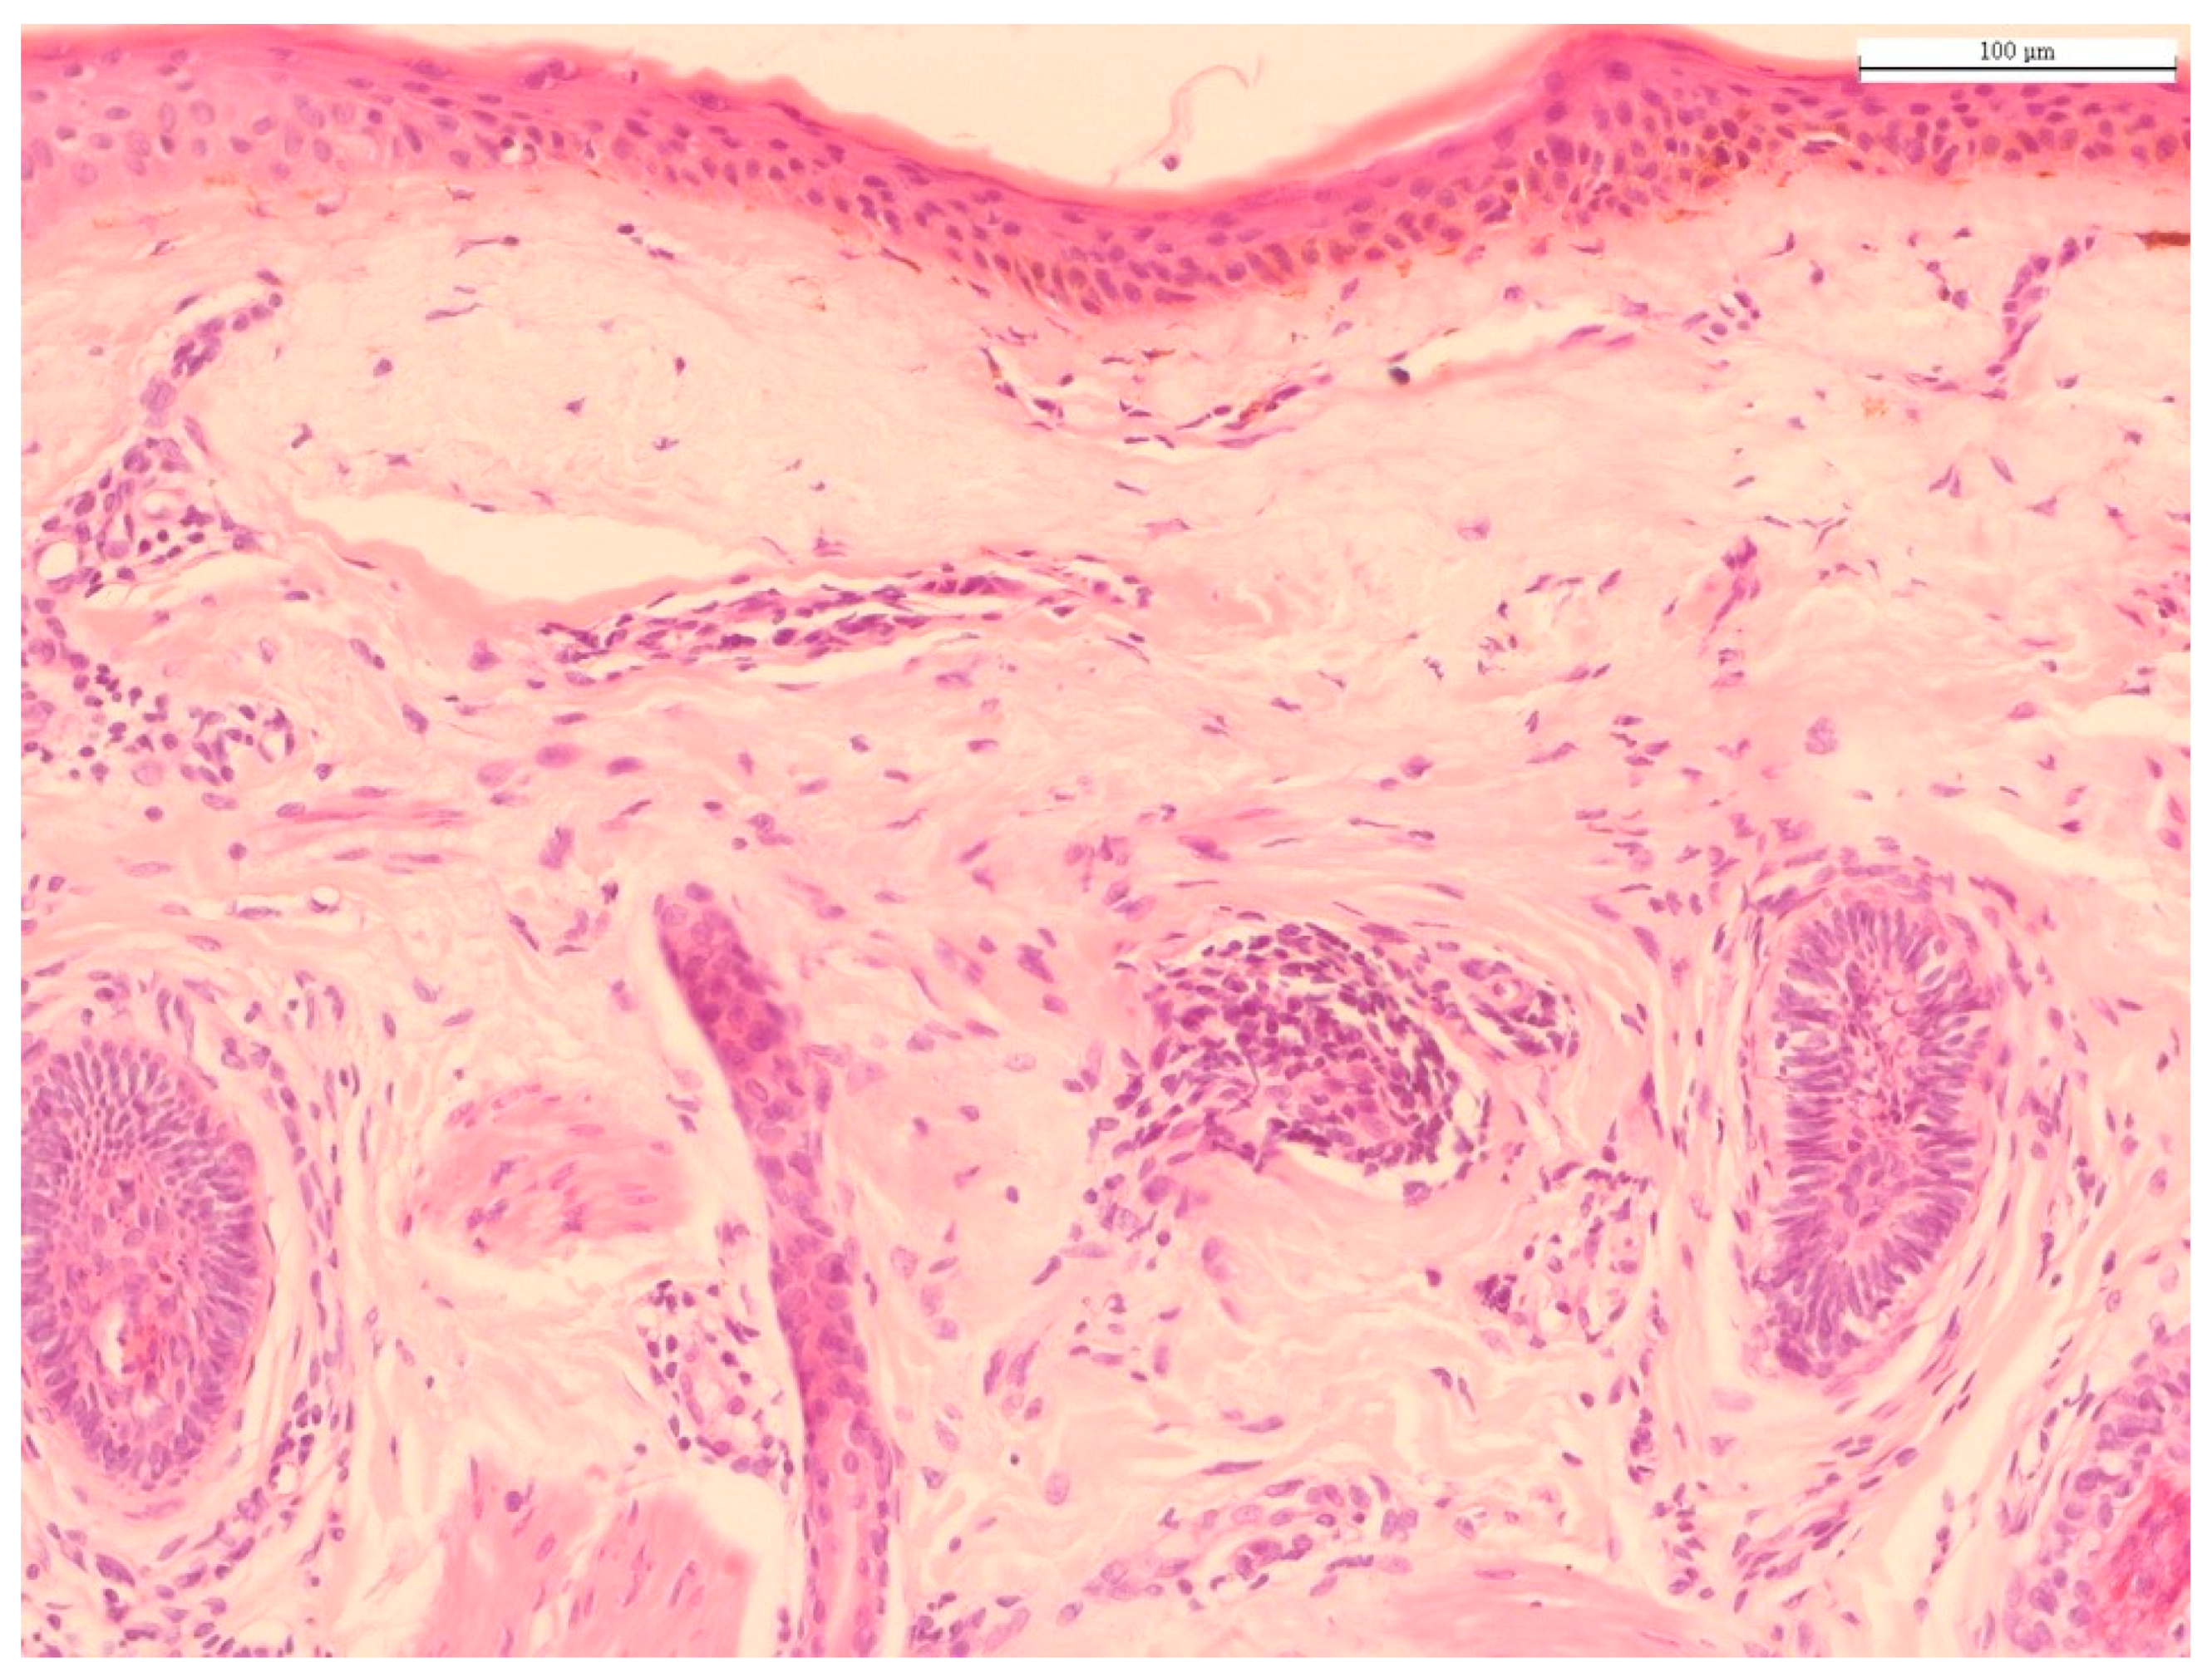

2. Histology of Chronological Aging and Photoaging